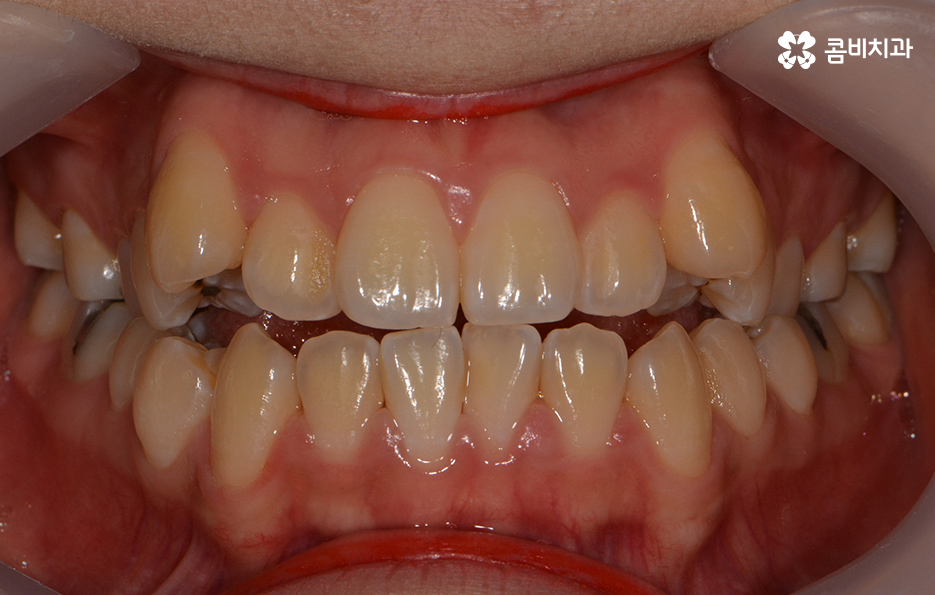

위 환자분의 경우에는 비발치로 송곳니 덧니 교정이

진행된 사례이며 전체 진료 기간은 약 1년 6개월가량이 소요되었습니다.

클리피씨 교정을 통해서 덧니가 개선되고 있는 경과